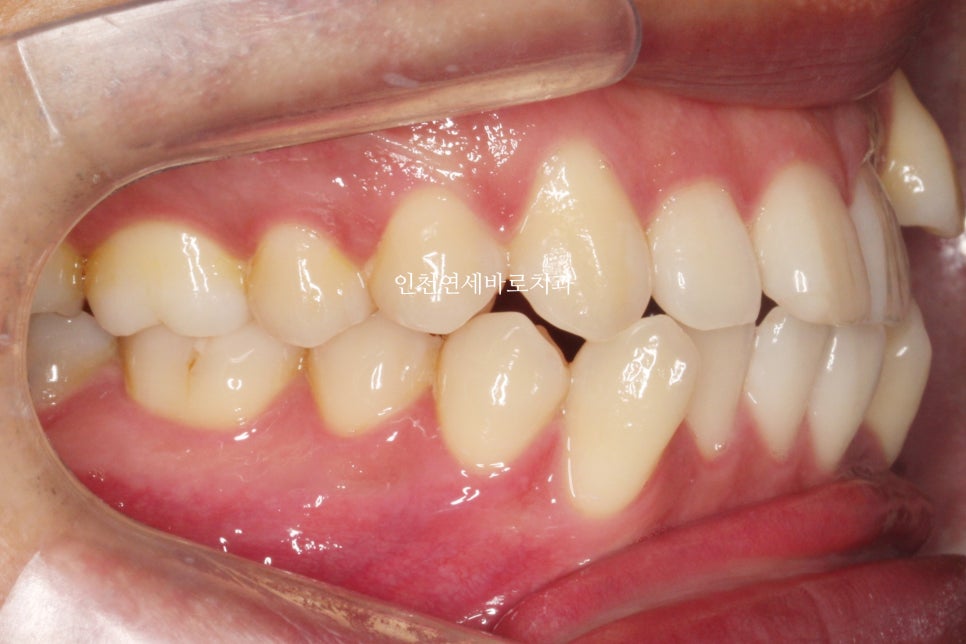

발치 교정으로 인비절라인 끝난 환자분으로

오른쪽은 그냥 돌출입의 교정

왼쪽은 덧니의 발치교정으로

좌 우를 보면 인비절라인과 관련된 모든 발치교정 이야기를 할 수 있을 것 같네요

약 7개월이 지난 후의 사진인데 벌써 많은 양의 덧니가 해결되었네요

약 1년 4개월이 지난 모습입니다.